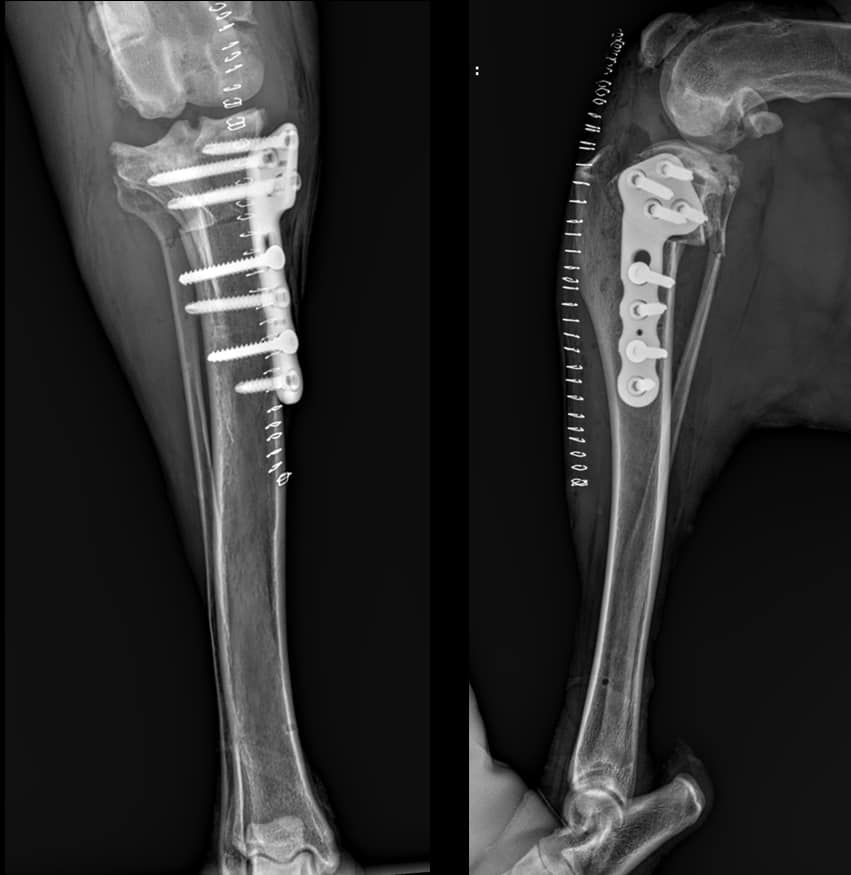

🔹 Płyty dostępne są w dwóch rozmiarach: 90 mm i 98 mm.

🔩 Wkręty blokowane 5.0 i korowe 4.5 do płyt oferujemy z gniazdem sześciokątnym lub TORX.

Dziękujemy serdecznie dr n. wet. Piotrowi Trębaczowi za udostępnione zdjęcia RTG.